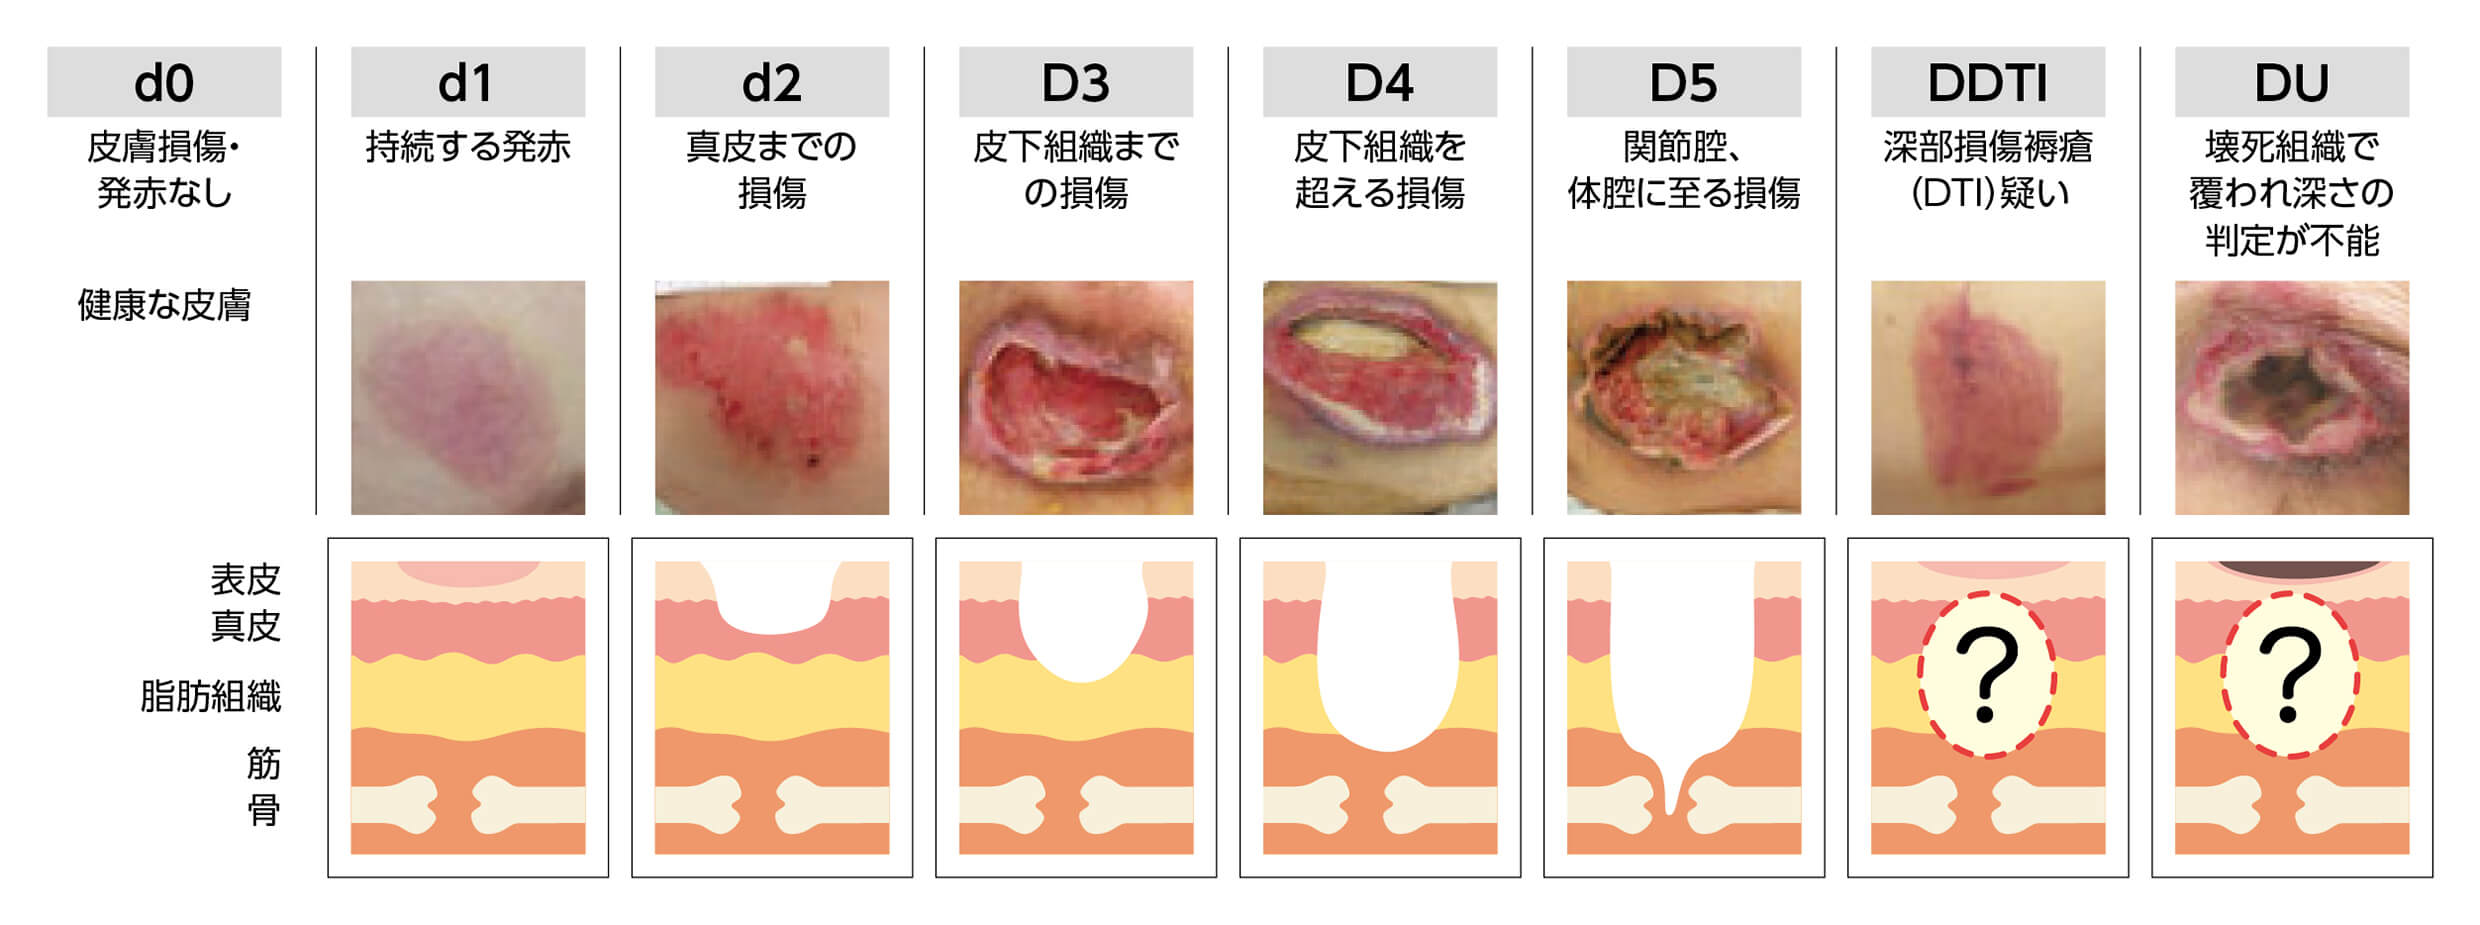

褥瘡の重症度分類を理解しようステージ分類NPUAP、EPUAP分類。

急性期の褥瘡と慢性期の褥瘡とは浅い褥瘡、深い褥瘡進展過程。

褥瘡治療① 実はあまり知られていない必須の褥瘡知識:褥瘡の治療法は深さによって異なる! -皮膚科専門医が伝授!医療従事者のための高齢者皮膚トラブル対策講座。

褥瘡治療① 実はあまり知られていない必須の褥瘡知識:褥瘡の治療法は深さによって異なる! -皮膚科専門医が伝授!医療従事者のための高齢者皮膚トラブル対策講座。

急性期の褥瘡と慢性期の褥瘡とは浅い褥瘡、深い褥瘡進展過程。

褥瘡治療① 実はあまり知られていない必須の褥瘡知識:褥瘡の治療法は深さによって異なる! -皮膚科専門医が伝授!医療従事者のための高齢者皮膚トラブル対策講座。

医師監修・作成 褥瘡 床ずれ の検査や分類などMEDLEY メドレー。